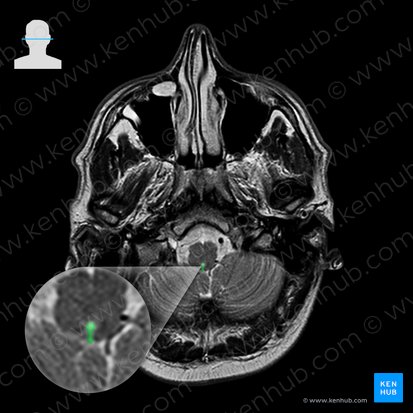

Cross-section

The layout of tracts and nuclei varies from one level of the brainstem to the other. As a result, the cross-sectional layout of the nuclei and tracts within the medulla may be slightly different going from the decussation of the pyramids to the level of the olives, for example.

The two main cross-sectional points that will be discussed in the medulla is at the level of the vagus (CN X) and hypoglossal (CN XII) nerves. Note that the nuclei and tracts that are discussed are paired structures present in both the left and right halves of the brainstem.

Cross section of medulla at the level of the vagus nerve (overview diagram)

Cross section of the medulla at the level of the hypoglossal nerve (overview diagram)